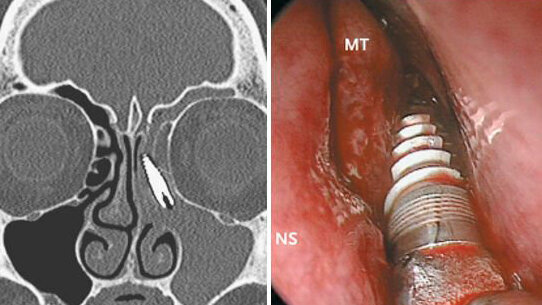

Secondo il caso, che è stato pubblicato online il 24 ottobre scorso sul New England Journal of Medicine da ricercatori del'Università di Brescia, la donna manifestava sinusite ricorrente del seno mascellare sinistro. Una CT ha rivelato la presenza di un corpo estraneo nel suo seno etmoidale sinistro.

Due anni prima, il paziente si era sottoposto all’inserimento di un impianto endosseo nella mascella superiore. Tuttavia, un attento esame aveva rivelato che non vi era nulla.

I medici hanno eseguito un intervento di chirurgia endoscopica ed estratto la protesi. Il paziente è stato dimesso il giorno dopo l’operazione, con rapido sollievo dei sintomi.

I ricercatori hanno concluso che lo spostamento dell’impianto dentale nel seno potrebbe essere stato causato da un posizionamento improprio o da una conseguenza tardiva di riassorbimento dell'osso e peri-implantite.